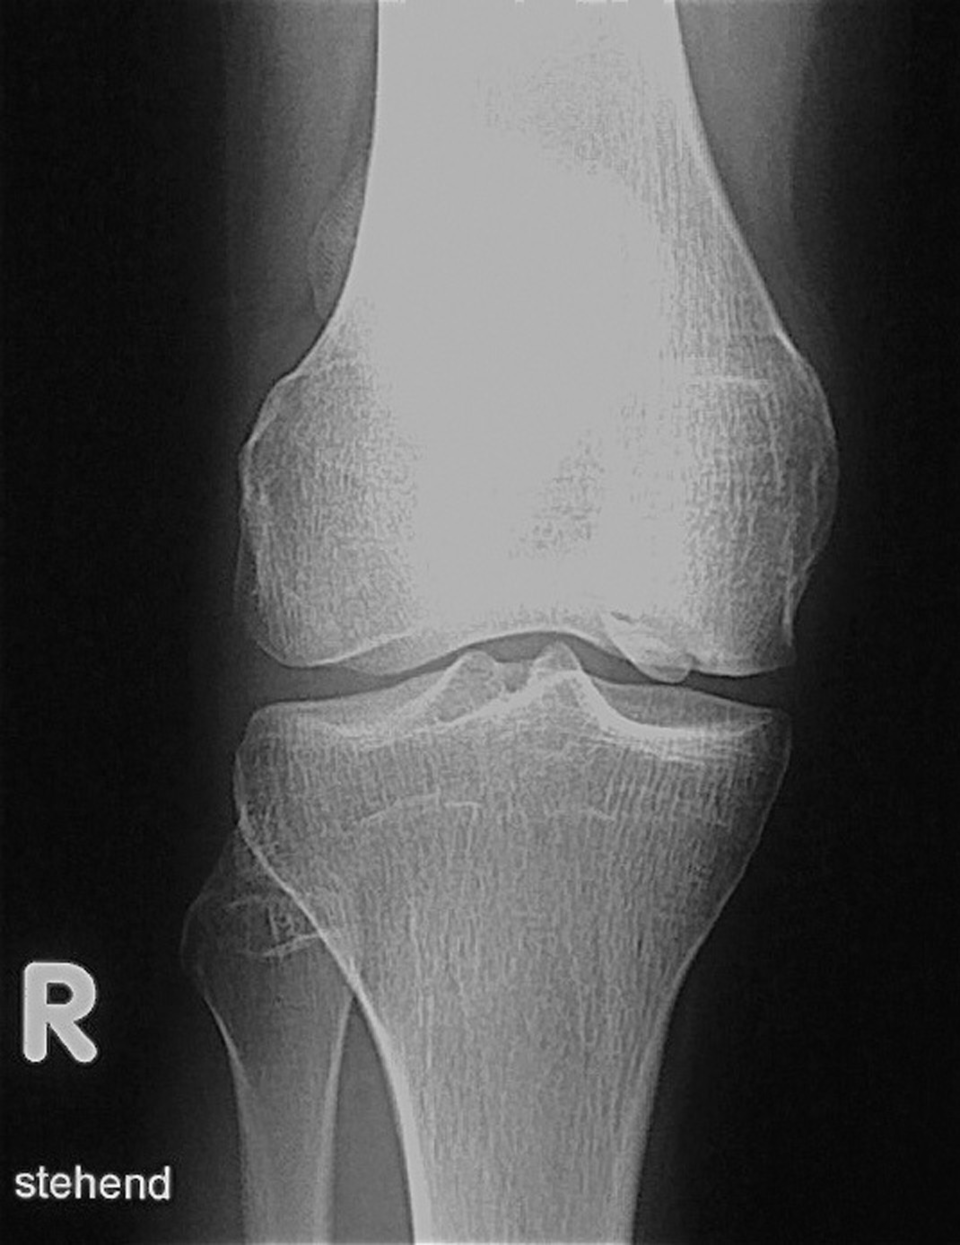

Der Morbus Blount, eine Wachstumsstörung der medialen Tibia-Epiphysenfuge, betrifft vor allem afrikanischstämmige Kinder. Der Morbus Blount, eine Wachstumsstörung der medialen Tibia-Epiphysenfuge, betrifft vor allem afrikanischstämmige Kinder. © wikimedia/Kinderradiologie Olgahospital Klinikum Stuttgart